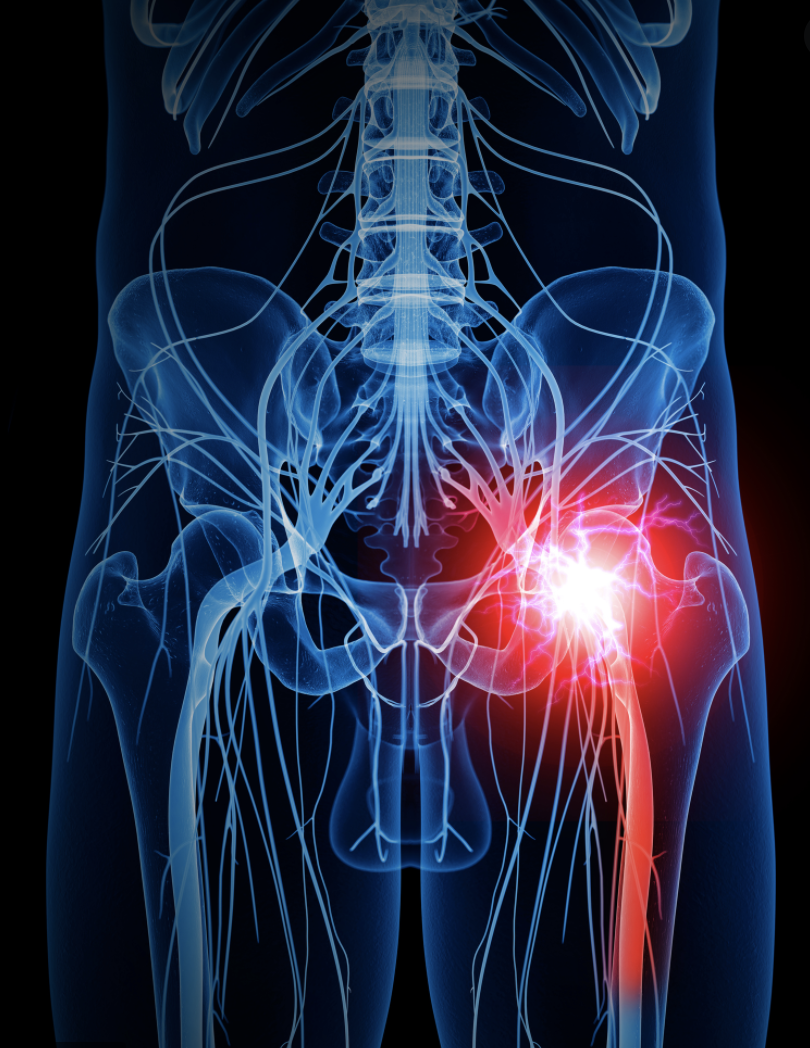

Lumbar radiculopathy, also known as “pinched nerve”, or “sciatica”, usually occurs when one of the spinal nerves exiting the spinal cord in the low back gets irritated or compressed. This can cause muscle weakness and pain that radiates into the buttock, upper thigh, leg, and/or foot and ankle regions. Lumbar radiculopathy can be either chronic or acute. With this condition, the leg pain is typically much worse than the low back pain. Specific areas of the leg and/or foot that are affected depends on which nerve in the low back is affected. Compression of higher lumbar nerve roots such as L2, L3 and L4 can cause radicular pain into the front of the thigh and the shin, where as compression of the lower lumbar and sacral nerve roots Such as L5, S1, and S2 can cause radicular pain into the back of the thigh, leg and foot.

Radicular pain radiates into the lower extremity directly along the affected spinal nerve root. The most common symptom of radicular pain is sciatica, causing pain radiating across the sciatic nerve into the back of the thigh and calf into the foot. Sciatica is one of the most common forms of pain caused by compression of a spinal nerve in the low back. It often will be caused by compression of the lower spinal nerve roots (L5 and S1). Chronic lumbar radiculopathy is often related to the normal aging and degenerative process that causes “wear and tear” changes in the spine, such as arthritis.